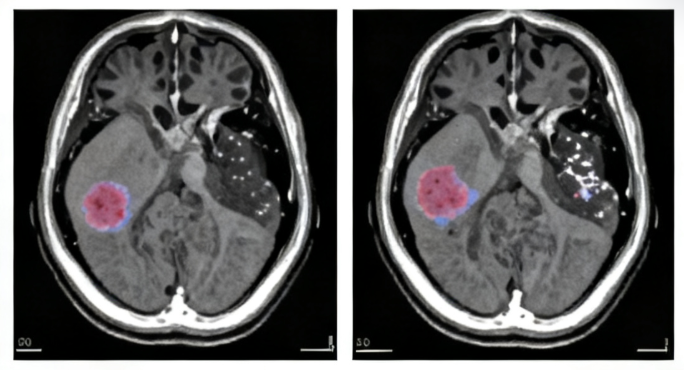

• MRI brain with contrast (to identify supratentorial mass)

ZFTA fusion–associated tumors are rare primary central nervous system (CNS) neoplasms characterized by gene fusions involving the ZFTA (formerly C11orf95) gene. These fusions most commonly occur with RELA or other partner genes and are often found in supratentorial ependymomas, particularly in children and young adults. The ZFTA fusion drives abnormal gene expression, promoting tumor development. These tumors can vary in aggressiveness but are generally considered high-grade (Grade III or IV).